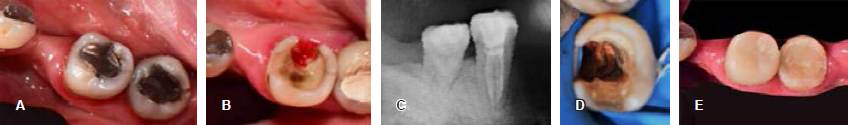

Mujer de 46 años de edad que acude a la Clínica de Odontología Restauradora Avanzada en el Postgrado de Odontología de la Facultad de Odontología de la UNAM, con el motivo de consulta de restaurar los dientes 36 y 37 (Figura 1A), despulpados, con restauraciones provisionales, lesiones de caries recidivante y espacio interoclusal disminuido en relación con sus antagonistas, tejido remanente coronario limitado en ambos dientes, pero en especial en el diente 36 y con un mínimo grosor a nivel de la furca, se indica su extracción para posterior colocación de implante. En el análisis del diente 37, éste contaba con altura de 4 mm y un grosor de 3 mm en todas sus paredes, por lo cual se determina la realización de una endocorona (Figura 1B).

Figura 1 A) Estado inicial de diente 37. B) Espacio interoclusal limitado que indica la realización de una endocorona. C) Divergencia de 5º a 8º con resina. D) Vista interna de la incrustación de cerómero. E y F) Vista vestibular y oclusal respectivamente de la endocorona ya cementada.

Con aislamiento absoluto, se procede a la preparación del espacio de la cámara pulpar, para crear divergencia oclusal entre 5 y 8 grados, descontaminación con hipoclorito de sodio al 5% y compensación de socavados con resina fotocurable FiltekTM Z350 (3M- ESPE) brindando paredes rectas y lograr la divergencia mencionada, se sellaron los accesos de conductos con cemento polimérico RelyXTM U200 (3M-ESPE), se procedió a tomar impresión con polivinil siloxano (PVS), Elite HD+ (Zhermack) (Figura 1C) y se realiza la obturación temporaria con Systemp onlay (Ivoclar Vivadent). El material restaurativo de elección fue cerómero SR Nexco (Ivoclar Vivadent) por sus características en general y en especial por su resiliencia, resistencia a la fractura y bajo costo (Figura 1D).

En la segunda cita se retira el restaurador temporario, se coloca el aislamiento absoluto, limpieza de la cavidad con clorhexidina en pasta al 2% ConsepsisTM Scrub (Ultradent), se comprueba la adaptación y la altura oclusal de la restauración y se procede a la cementación con RelyXTM U200 (3M-ESPE), se procede a la remoción de excedentes después de un prepolimerizado de 3 segundos, se retira el aislamiento absoluto, se comprueba la oclusión con papel articular de 12 μm, se realizó el pulido con gomas y pasta de pulido para resinas (Figura 1E-F).